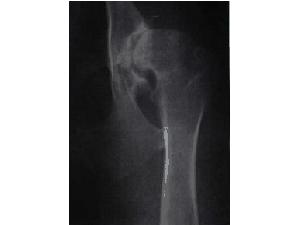

DKK - dysplazie kyčelních kloubů

Vývojová vada postihující hlavně velké rasy psů. Kloub a kloubní jamka do sebe přesně nezapadají, nebo nejsou dostatečně vyvinuty.

Označování: pravá/levá<br />

0 (A) - bez vady<br />

1 (B) - přechod mezi bezvadným a lehkou DKK<br />

2 (C) - lehká DKK<br />

3 (D) - střední DKK<br />

4 (E) - těžká DKK